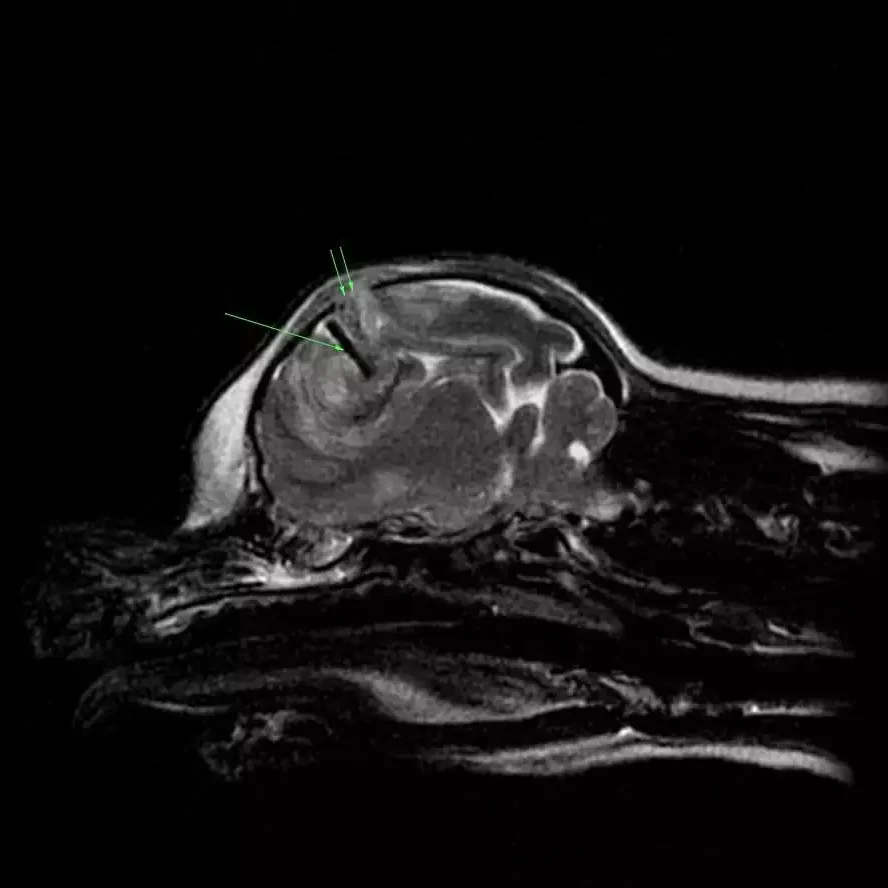

MRI image of a small dog with head trauma after being bitten by a larger dog. Note the bone fragment (single arrow) that is within the brain parenchyma. The double arrows show the defect in the skull.

Head Trauma

Rarely, brain surgery is needed following head trauma if there is excessive bleeding in the brain, broken bones of the skull, or foreign objects (bullets, broken tooth, dirt and debris) lodged in the brain. The likelihood of success depends on many factors, which your vet neurologist will discuss with you in detail based on your particular pet’s situation.